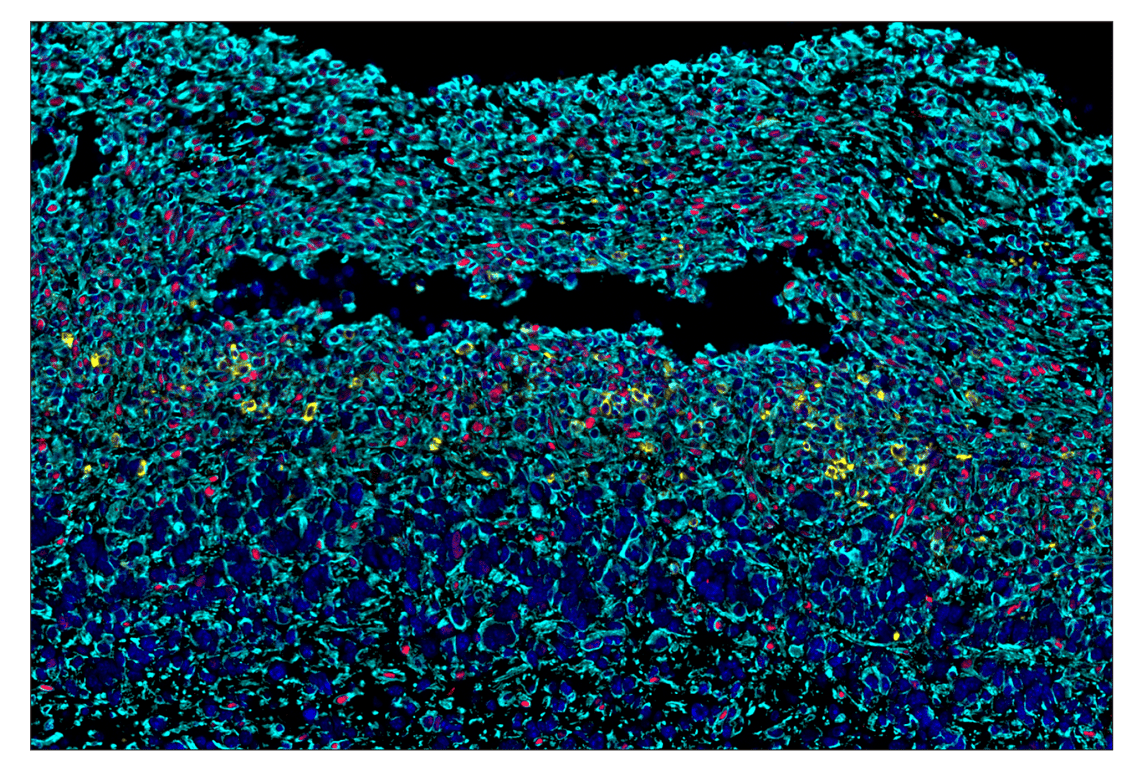

SignalStar™ multiplex immunohistochemical analysis of paraffin-embedded human gastric adenocarcinoma using Phospho-Stat3 (Tyr705) (D3A7) & CO-0029-594 SignalStar™ Oligo-Antibody Pair #86323 (yellow), Pan-Keratin (C11) & CO-0003-488 SignalStar™ Oligo-Antibody Pair #63566 (green), Tox/Tox2 (E6I3Q) & CO-0016-488 SignalStar™ Oligo-Antibody Pair #31189 (magenta), α-Smooth Muscle Actin (D4K9N) & CO-0024-647 SignalStar™ Oligo-Antibody Pair #63902 (red), CD163 (D6U1J) & CO-0022-750 SignalStar™ Oligo-Antibody Pair #71043 (cyan), and ProLong Gold Antifade Reagent with DAPI #8961 (blue). All fluorophores have been assigned a pseudocolor, as indicated. Staining was performed on the BOND RX by Leica Biosystems.

Immunohistochemistry Image 1: Phospho-Stat3 (Tyr705) (D3A7) & CO-0029-488 SignalStar<sup>™</sup> Oligo-Antibody Pair